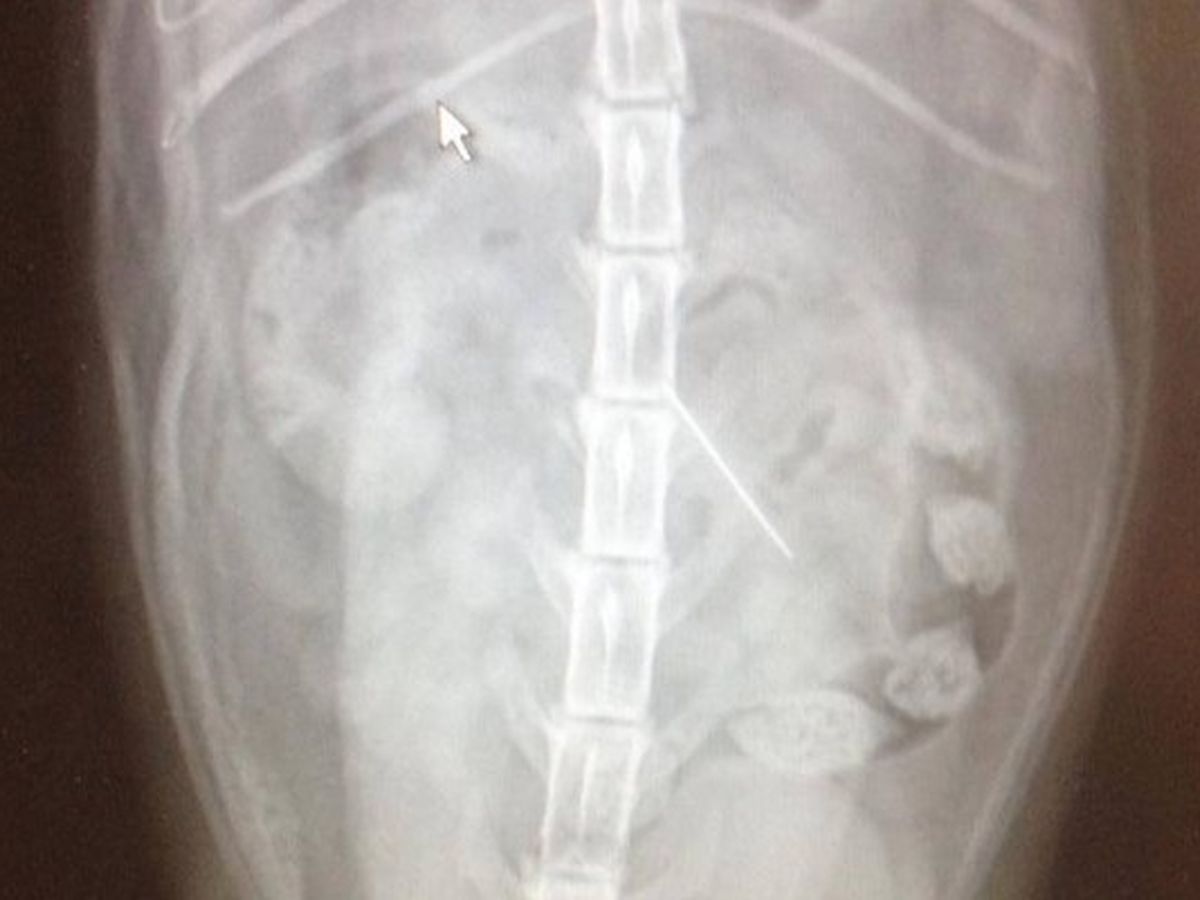

Prim is my cat and she is only two and a half years old. She swallowed a needle and thread, and she needs surgery immediately. I cannot afford a $3000 surgery by myself, and it would be a cruel reason to have to put her down because I can't afford her surgery. Please help me keep this furry member of my family. Please help me save her.